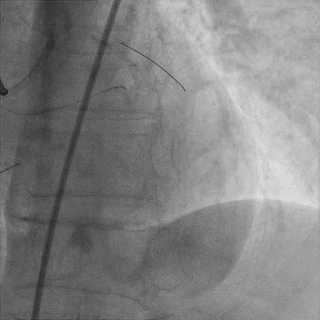

对角支送入IVUS导管,在IVUS实时指引下用尝试穿刺闭塞段

导丝未能进入闭塞段,导丝进入间隔支

逆向造影指引下继续尝试穿刺闭塞段

导丝远端与逆向造影不重叠,未在血管真腔

反复调整导丝最终进入D2#,可见导丝远端与D2侧枝重叠,证明远端位于真腔